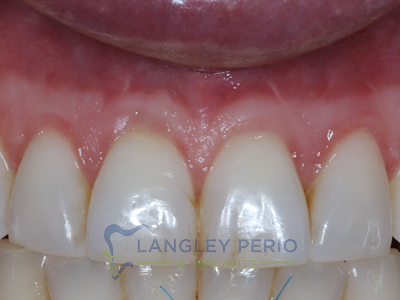

Case 3

Alloderm tissue grafting performed to improve root coverage and esthetics. This technique does not require tissue to be taken from the patient’s palate.